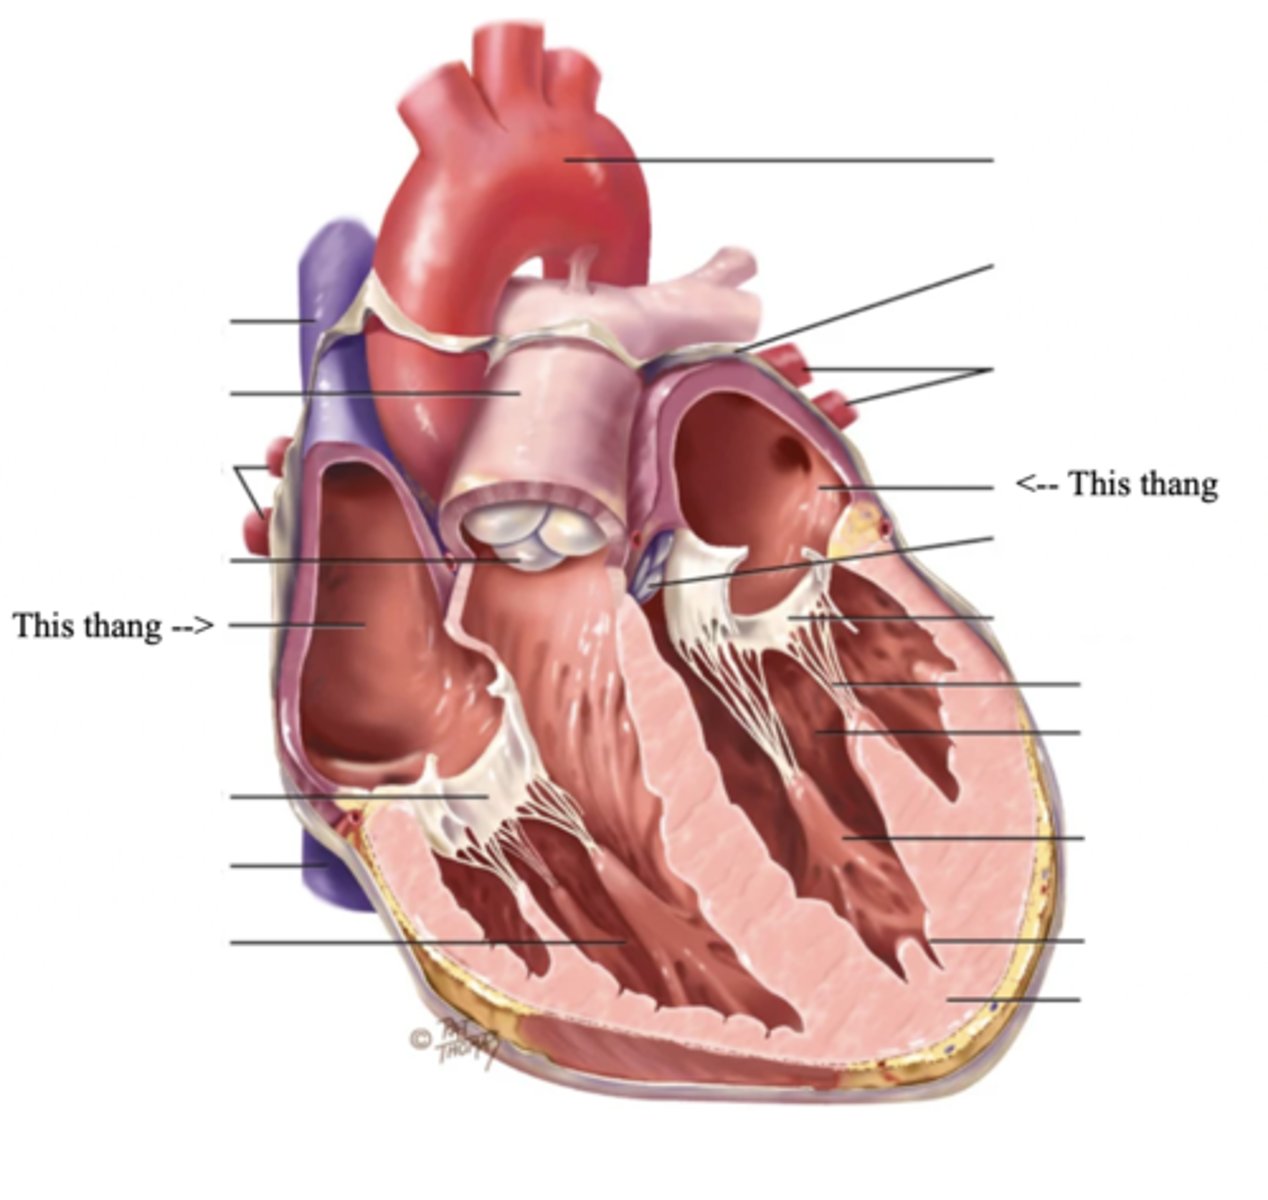

Anatomy of the Heart

3 Layers of the Heart Wall

- Pericardium

- Myocardium

- Endocardium

Pericardium

Myocardium

The muscular wall of the heart; does the pumping

Endocardium

The thin layer of endothelial tissue that lines the inner surface of the heart chambers and valves

2 Types of Chambers in the Heart

- Atrium

- Ventricles

Atrium (2)

A thin-walled reservoir for holding blood, located at the upper chamber of the heart

Ventricle (2)

The thick walled muscular pumping chamber of the heart located at the bottom chamber of the heart

2 Main Types of Valves of the Heart

- Atrioventicular

- Semilunar

Atrioventricular Valves (AV) (2)

The valves that separate the atria and the ventricles

The 2 Atrioventicular Valves of the Heart

- Tricuspid

- Mitral

Tricuspid Valve

- The right AV valve separating the right atrium from the right ventricle

- Connected by 3 chordae tendinae

Mitral (Bicuspid) Valve

- The left AV valve separating the left atrium from the left ventricle

- Connected by 2 chordae tendinae

Chordae Tendinae

Fibers (heart strings) attatched to the tricuspid and mitral valve which pull it closed when papillary muscles contract, preventing back flow of blood

Semilunar Valves (SV) (2)

Valves located between the ventricles and the pulmonary arteries and aorta

The 2 Semilunar Valves of the Heart

- Pulmonic

- Aortic

Pulmonic Valve

The SV valve of the right side of the heart

Aortic Valve

The SV valve of the left side of the heart

The 4 Great Vessels of the Heart

- Superior/inferior venae cavae

- Pulmonary artery

- Pulmonary veins

- Aorta

Superior/Inferior Venae Cavae

The large veins that empty into the right atrium of the heart and return unoxygenated venous blood to the right side of the heart

Pulmonary Artery

Artery carrying oxygen-poor blood from the heart to the lungs

Pulmonary Veins

Veins carrying oxygenated blood from the lungs to the heart

Aorta

The largest artery in the body which carries oxygenated blood from the heart throughout the body